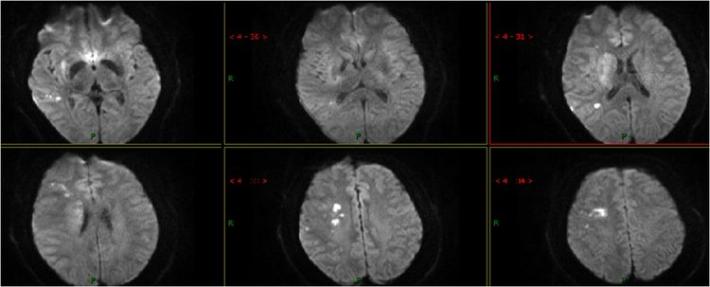

术后8天复查头部MRI

查体:患者神志清,精神可,双侧肢体肌力4级,NIHSS评分:4分,mRS:2分。